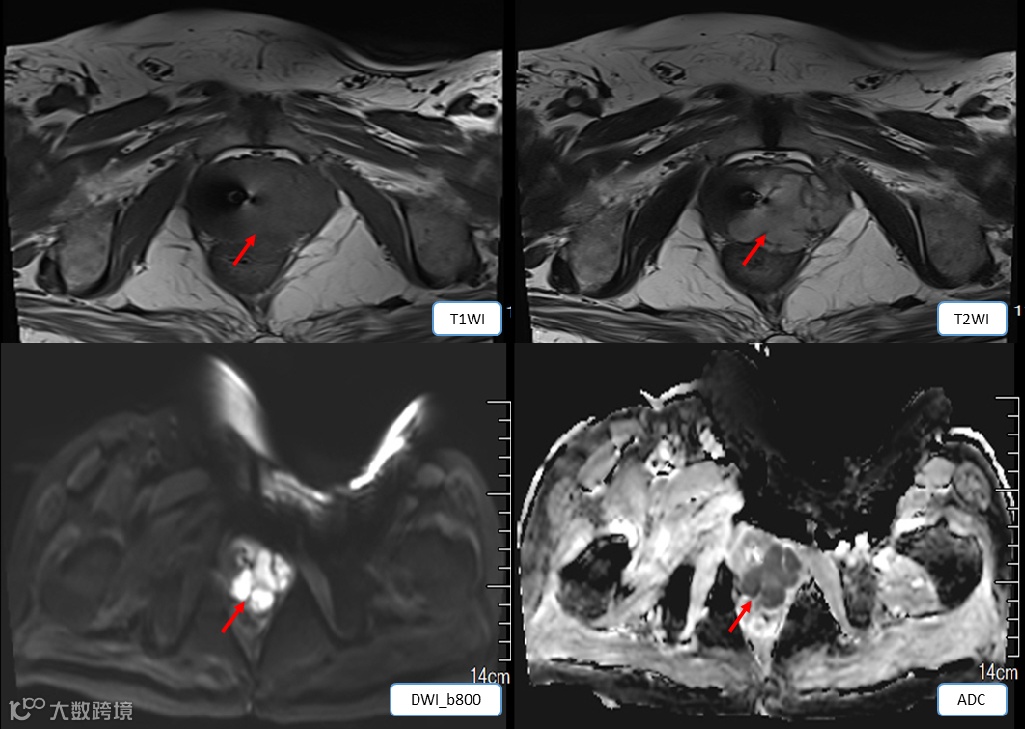

影像学表现